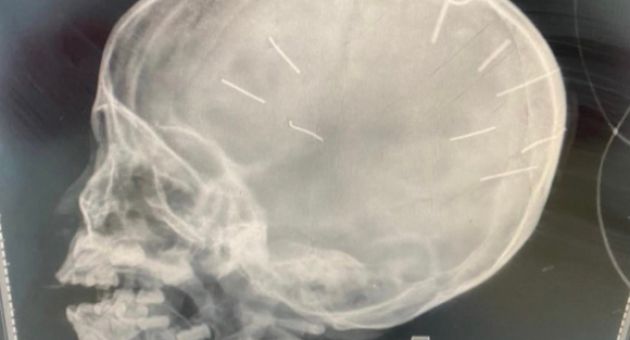

Công an huyện Thạch Thất đã bàn giao một nghi can cho Phòng cảnh sát hình sự, Công an Hà Nội để làm rõ vụ việc bé gái 3 tuổi nhập viện trong tình trạng có vật thể lạ giống đinh bị găm vào hộp sọ.